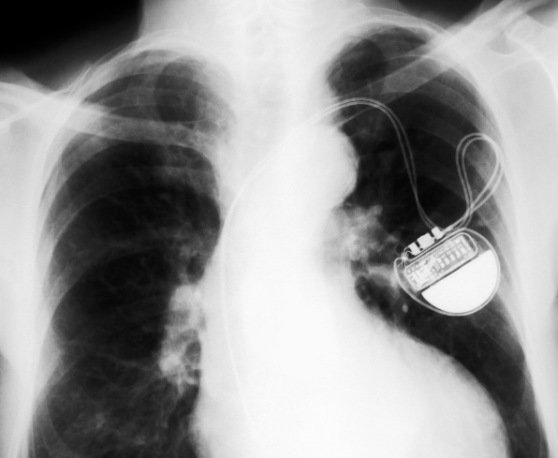

A small device implanted under the skin, designed to mimic the heart's natural pacemaker

When the heart natural " battery" becomes depleted , the artificial pacemaker is implanted to take over.